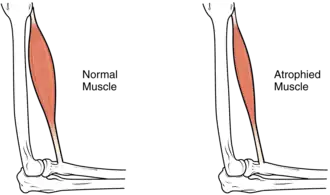

Muscle atrophy

In the long term, the loss of muscle function can have additional effects from disuse, including muscle atrophy. Immobility also can lead to pressure sores, particularly in bony areas, requiring precautions such as extra cushioning and turning in bed every two hours (in the acute setting) to relieve pressure.[52]

In the long term, people in wheelchairs must shift periodically to relieve pressure.[53] Another complication is pain, including nociceptive pain (indication of potential or actual tissue damage) and neuropathic pain, when nerves affected by damage convey erroneous pain signals in the absence of noxious stimuli.[54] Spasticity, the uncontrollable tensing of muscles below the level of injury, occurs in 65–78% of chronic SCI.[55] It results from lack of input from the brain that quells muscle responses to stretch reflexes.[56] It can be treated with drugs and physical therapy.[56] Spasticity increases the risk of contractures (shortening of muscles, tendons, or ligaments that result from lack of use of a limb); this problem can be prevented by moving the limb through its full range of motion multiple times a day.[57] Another problem lack of mobility can cause is loss of bone density and changes in bone structure.[58][59] Loss of bone density (bone demineralization), thought to be due to lack of input from weakened or paralysed muscles, can increase the risk of fractures.[60] Conversely, a poorly understood phenomenon is the overgrowth of bone tissue in soft tissue areas, called heterotopic ossification.[61] It occurs below the level of injury, possibly as a result of inflammation, and happens to a clinically significant extent in 27% of people.[61]